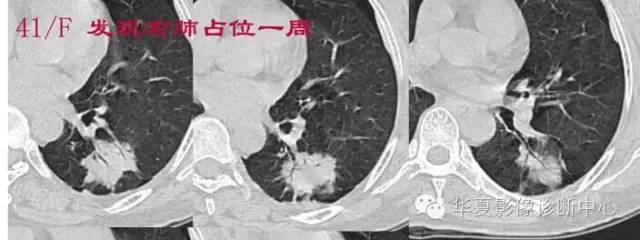

结果自然就倾向于癌

磨玻璃结节良恶性影像分析策略磨玻璃结节良恶性影像分析策略 这个按常规看到血管由凹陷处进去常规95%考虑癌,可是这里却不是

除非说这里GGO边缘稍模糊一些

宽基底与胸膜相连

近端有模糊的高密度影